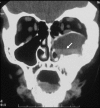

McCune-Albright syndrome (MAS) is classically defined by the clinical triad of fibrous dysplasia of bone (FD), café-au-lait skin spots, and precocious puberty (PP). It is a rare disease with estimated prevalence between 1/100,000 and 1/1,000,000. FD can involve a single or multiple skeletal sites and presents with a limp and/or pain, and, occasionally, a pathologic fracture. Scoliosis is common and may be progressive. In addition to PP (vaginal bleeding or spotting and development of breast tissue in girls, testicular and penile enlargement and precocious sexual behavior in boys), other hyperfunctioning endocrinopathies may be involved including hyperthyroidism, growth hormone excess, Cushing syndrome, and renal phosphate wasting. Café-au-lait spots usually appear in the neonatal period, but it is most often PP or FD that brings the child to medical attention. Renal involvement is seen in approximately 50% of the patients with MAS. The disease results from somatic mutations of the GNAS gene, specifically mutations in the cAMP regulating protein, Gs alpha. The extent of the disease is determined by the proliferation, migration and survival of the cell in which the mutation spontaneously occurs during embryonic development. Diagnosis of MAS is usually established on clinical grounds. Plain radiographs are often sufficient to make the diagnosis of FD and biopsy of FD lesions can confirm the diagnosis. The evaluation of patients with MAS should be guided by knowledge of the spectrum of tissues that may be involved, with specific testing for each. Genetic testing is possible, but is not routinely available. Genetic counseling, however, should be offered. Differential diagnoses include neurofibromatosis, osteofibrous dysplasia, non-ossifying fibromas, idiopathic central precocious puberty, and ovarian neoplasm. Treatment is dictated by the tissues affected, and the extent to which they are affected. Generally, some form of surgical intervention is recommended. Bisphosphonates are frequently used in the treatment of FD. Strengthening exercises are recommended to help maintaining the musculature around the FD bone and minimize the risk for fracture. Treatment of all endocrinopathies is required. Malignancies associated with MAS are distinctly rare occurrences. Malignant transformation of FD lesions occurs in probably less than 1% of the cases of MAS.